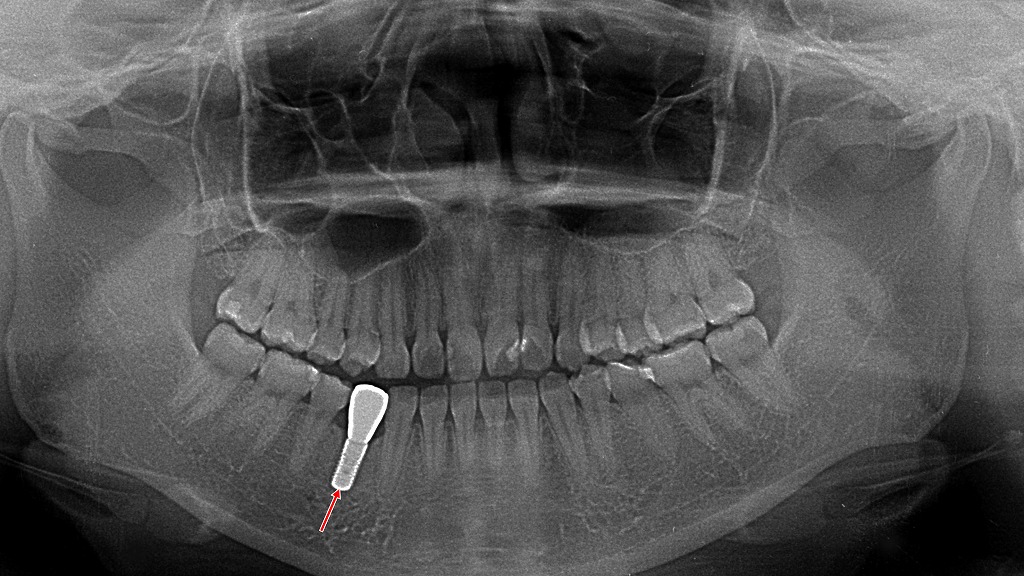

歯の根っこまで破折している場合は、残念ながら抜歯が必要になることも。その場合はブリッジ・入れ歯・インプラントといった選択肢から治療法を選びます。特にインプラントは機能性・審美性の両面で優れています💡。

赤矢印が示す部分では、歯の根(歯根)が折れており、この状態は修復や根管治療では保存が不可能です。歯根破折は進行性で、細菌感染が広がるため、このケースの場合“抜歯が唯一の適切な治療”となります。

上顎前歯が破折して抜歯に至った症例。欠損後の歯槽堤は比較的保たれていたものの、審美性と長期安定性を確保するため、適正な埋入位置を考慮した二本のインプラント埋入と同時の骨造成(GBR)を実施した。術前の軟組織形態から、埋入後の骨補填材によるボリューム再建まで一連の処置を示しており、前歯部インプラントに求められる骨量確保と精密な三次元的ポジショニングの重要性がわかる症例である。